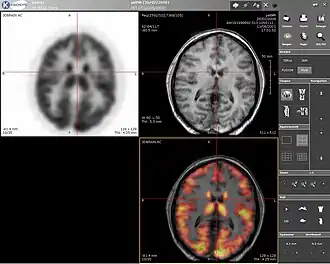

Positron emission tomography

Positron emission tomography (PET) is a nuclear medicine imaging technique which produces a three-dimensional image or picture of functional processes in the body. The theory behind PET is simple enough. First a molecule is tagged with a positron emitting isotope. These positrons annihilate with nearby electrons, emitting two 511 keV photons, directed 180 degrees apart in opposite directions. These photons are then detected by the scanner, which can estimate the density of positron annihilations in a specific area. When enough interactions and annihilations have occurred, the density of the original molecule may be measured in that area. Typical isotopes include 11

F being the most clinically utilized. One of the major disadvantages of PET is that most of the probes must be made with a cyclotron. Most of these probes also have a half life measured in hours, forcing the cyclotron to be on site. These factors can make PET prohibitively expensive. PET imaging does have many advantages though. First and foremost is its sensitivity: a typical PET scanner can detect between 10−11 mol/L to 10−12 mol/L concentrations.